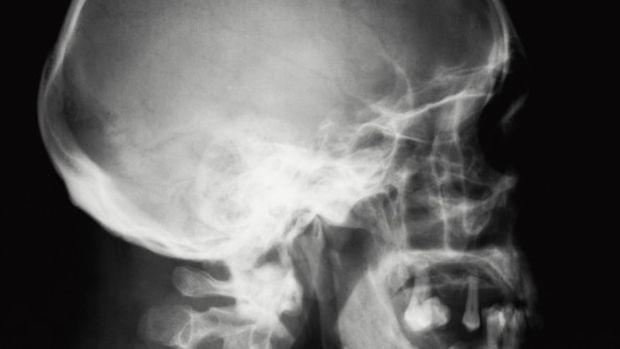

Zaustavio se točno između drugog oko i mozga. Operacija je bila vrlo složena jer je falio milimetar da završi kobno.

Liječnici su 27-godišnjem muškarcu izvadili čavao iz glave, a osam tjedana kasnije on se vratio u normalu. No, liječnici su rekli da mu je čavao ušao samo milimetar dalje vjerojatno bi pretrpio veliku štetu. Bostonski liječnici strahovali su da ne dođe do krvarenja, no operacija je uspješno obavljena. Taj slučaj se dogodio prije dvije godine.

Neurokirurg Dr. Wael Asaad ispričao je da su prilikom operacije morali biti vrlo oprezni prilikom izvlačenja.

"Tu je moglo biti jakog krvarenja zbog puknuće arterije, a moglo se oštetiti drugo oko ili mozak, i operacija je mogla završiti kobno.", kazao je Asaad.